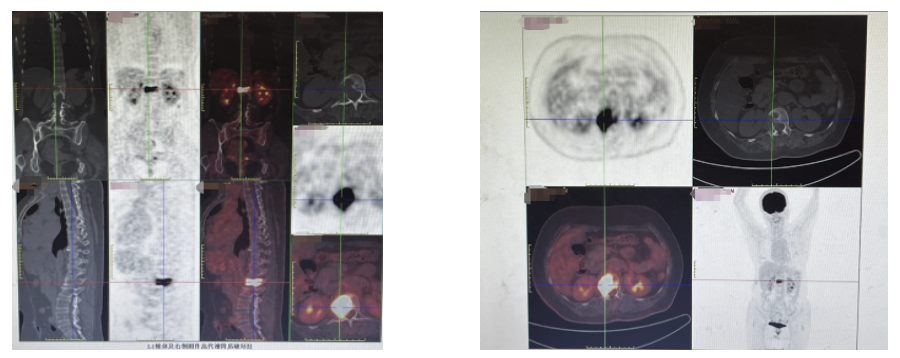

胸腰椎MR示: L1椎体及附件、L2椎体、L3棘突信号异常,考虑转移瘤可能性大。

PET-CT示:L1骨质破坏伴代谢增高,考虑为转移所致可能性大。